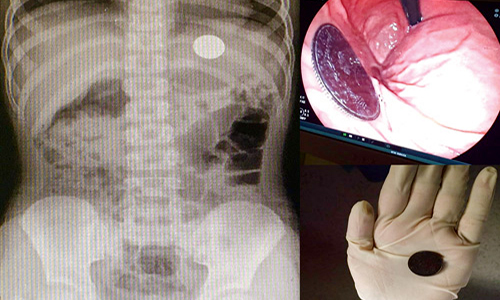

أُجريت بمستشفى الولادة والأطفال ببريدة عملية بالمنظار لطفل يبلغ من العمر 7 سنوات، عبر وحدة مناظير الجهاز الهضمي وقسم جراحة الأطفال؛ لاستخراج عُملة معدنية بقيادة رئيس قسم وحدة مناظير الجهاز الهضمي الاستشاري د. عبد العزيز الحربي، الذي أوضح أنه تم إجراء العملية بنجاح، والطفل بصحة جيدة. منبهًا في الوقت نفسه إلى ضرورة الاهتمام بمتابعة الأطفال وما يضعونه في أفواههم؛ حتى لا يتعرضوا للاختناق أو مضاعفات العمليات نتيجة استخراجها.